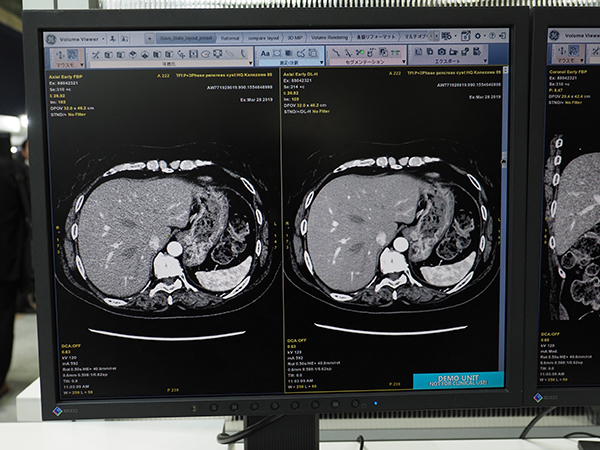

GE社は,RSNA 2018において,GE創業者のトーマス・エジソンの名を冠した人工知能(AI)とbusiness intelligence(BI)のプラットフォーム「Edison」を紹介したが,ITEM 2019では,そのEdison Platformを用いて開発されたCT画像再構成技アルゴリズム「TrueFidelity」を発表した。TrueFidelityは,ディープラーニングを用いて開発されており,従来の画像再構成技術とは一線を画している。従来の画像再構成技術を用いたCT画像は,画質が読影する医師にとって違和感のあるテクスチャとなってしまい,特にノイズを低減すればするほど,その傾向が強くなるという課題があった。そこで,TrueFidelityでは,FBP法で高線量で撮影した診断に適した画像を教師画像としてディープラーニングを行った。これにより,大幅に線量を落としても,高線量で撮影を行ったような鮮明な画質を得ることができる。また,全身の撮影に適用できるのも,TrueFidelityの特長である。特に,高い密度分解能が要求される頭部や腹部領域の検査で,画質を維持しつつノイズを低減し,読影する医師の負担軽減や診断能の向上に寄与する。放射線被ばくの感受性が高い小児検査でも大幅な被ばく低減が可能となる。TrueFidelityは,ハイエンド装置の「Revolution CT」に搭載可能である。オプションとして提供されるほか,すでにRevolution CTを導入している施設には,アップグレードで対応可能となっている。

「TrueFidelity」(右)は大幅にノイズ低減を実現